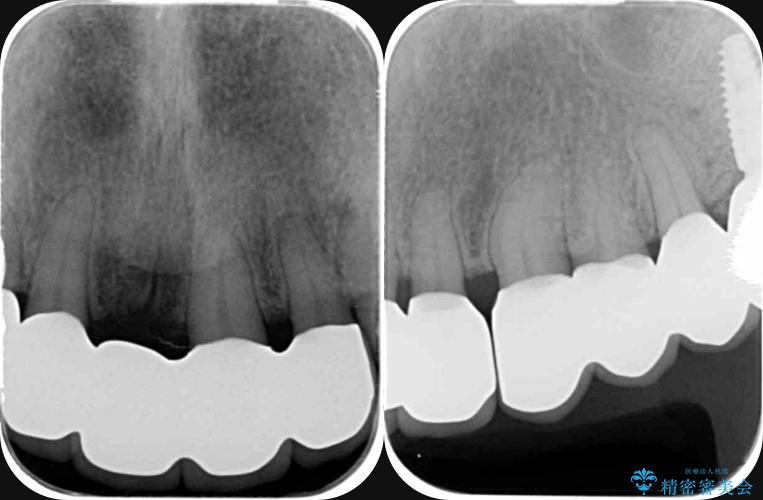

検査の結果、歯周ポケットの測定値は4-6mm程度の値が全顎にわたって認められ、中等度歯周病の状態です。

歯を今後残し、歯周病の状態を改善するため、歯槽骨の再生治療をおこなったのち、歯周ポケットの除去、セラミックブリッジの製作を行う治療計画を実行していきます。

歯周病によって失われた歯を支える骨(歯槽骨)に対し、再生療法を用いることで骨の再生・回復を実現しました。骨の高さが改善されたことで、歯の土台が強化され、将来にわたって歯をしっかりと支え続けられる口腔内環境を整えることができました。